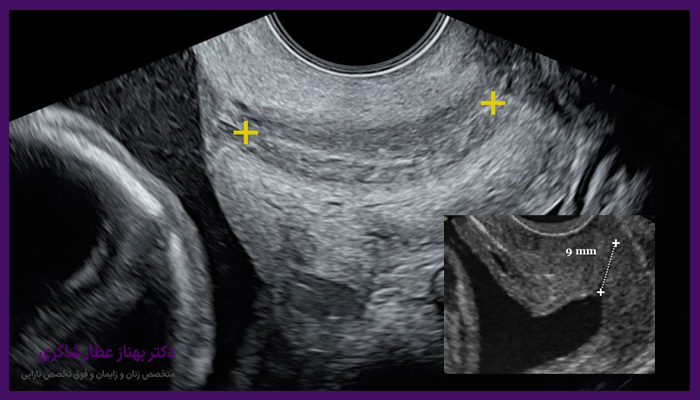

عموما طول سرویکس در دوران بارداری بهتدریج کاهش مییابد. این کاهش طبیعی به بدن برای آمادهسازی زایمان کمک میکند. اما اگر این کاهش زودتر از موعد رخ دهد، ممکن است نیاز به پیگیری جدی پزشکی باشد. در سونوگرافی واژینال میتوان این تغییرات را بهدقت بررسی کرد.

طول مناسب سرویکس به معنی حمایت کافی از جنین است. کوتاه شدن غیرعادی این ناحیه میتواند منجر به باز شدن زودهنگام دهانه رحم و در نتیجه زایمان زودرس یا حتی از دست دادن جنین شود. به همین دلیل، بررسی این طول در هفتههای میانی بارداری از طریق سونوگرافی واژینال توصیه میشود.

5- کنترل و پایش منظم با سونوگرافی

یکی از اقدامات حیاتی در صورت کوتاه بودن طول سرویکس، انجام سونوگرافیهای واژینال دورهای است تا وضعیت بهدقت بررسی شود و در صورت نیاز درمانهای تکمیلی انجام شود.